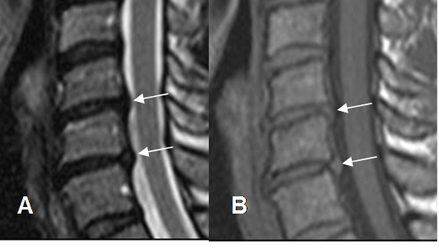

Fig 49. Prominencia del disco.

A: RM sagital en T2. Prominencia de los complejos disco ligamento, pero sin indentar el saco dural.

B: RM sagital en gradiente eco. Estas imágenes siguen la señal del disco. Corresponden a prominencias del disco y no a osteofitos.